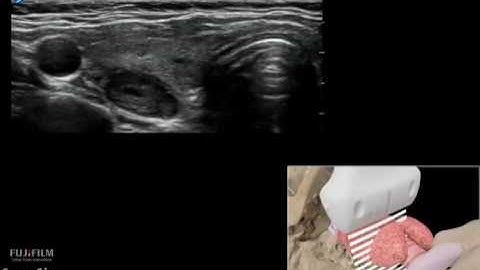

3D Segmentation of Thyroid Ultrasound Images using Active Constours in Matlab